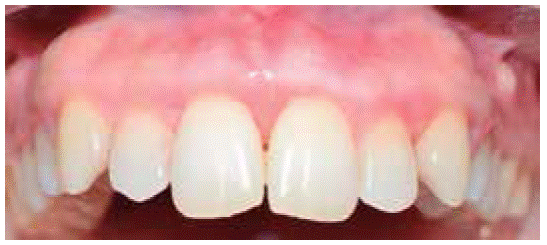

Favorable evolution was observed in the next controls, oral hygiene levels were more satisfactory, lesion did not relapse up to a seven month follow up period (Figure 16).

Controls: decrease of inflammatory circumstances of the wound area was observed after one week (Figure 20). Favorable evolution was observed in the following controls, more suitable oral hygiene levels were observed as well as lack of lesion recurrence, up to a six month follow-up period.

Evolution was favorable, with better maintenance of oral hygiene levels, and with no lesion recurrence up to a six month follow-up period.

Controls: suitable evolution and healing wound were observed after one week. Five months later, no lesion recurrence was observed.